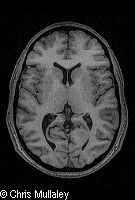

Según el criterio de un grupo de investigadores españoles, un extracto activo de la planta del cannabis podría ser utilizado para reducir el tamaño de tumores cerebrales y otros tipos de cáncer, al restringir su capacidad de aumentar los vasos sanguíneos para alimentarse. Según la publicación New Scientist, Manuel Guzmán y sus colegas de la Universidad Complutense de Madrid utilizaron el extracto de cannabis delta-9- tretahidrocannabinol en ratones y voluntarios humanos con el objetivo de bloquear un químico necesario para la angiogénesis, capacidad de los tumores para formar vasos sanguíneos. El extracto demostró su eficacia incluso en pacientes con el tipo de cáncer cerebral más agresivo. El equipo subraya que los resultados son preliminares y que el estudio está en desarrollo, aún así lo describen como un buen punto de partida. Cristina Blázquez, miembro del equipo, declaró a New Scientist: "el cannabinoide inhibe el efecto de la angiogénesis. Si un tumor no realiza la angiogénesis, no crece. De modo que si por un lado podemos mejorar la angiogénesis y por otro matar las células cancerígenas, podemos intentar crear una terapia para el cáncer". Para la obtención de estos resultados el equipo examinó los resultados del extracto de marihuana en 30 ratones. Observaron que bloqueaba la expresión de varios genes relacionados con la producción del factor de crecimiento endotelial vascular (VEGF). El VEGF es necesario para la angiogénesis, ya que posibilita que el tumor desarrolle una cadena de vasos sanguíneos para fortalecer su crecimiento. En los ratones y en dos pacientes humanos con cáncer cerebral, el cannabinoide disminuyó notablemente la actividad del VEGF. Observamos que los tumores de los ratones eran más pequeños y ligeramente pálidos"aseguró Blázquez, añadiendo que la palidez reflejaba su falta de aporte de sangre. Sobre el tratamiento en pacientes humanos, declaró parece funcionar pero aún es demasiado pronto. Richard Sullivan, jefe de los Programas Químicos de Investigación sobre el Cáncer en el Reino Unido, afirmó que esta investigación proporciona un nuevo compuesto básico para drogas anti-cáncer dirigidas al abastecimiento de sangre del tumor. Aunque este trabajo se encuentra en una primera etapa de desarrollo, otras investigaciones han demostrado que el VEGF es un importante objetivo para los medicamentos en varios tipos de cáncer.